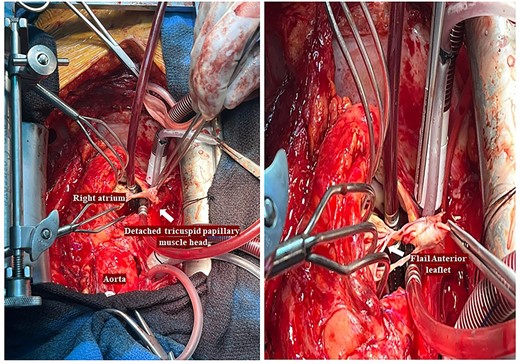

A 29-year-old man with a history of ventricular septal defect closure as a child, presented with severe multi-organ injuries after being run down by two cars. He was intubated on the scene by the hospital emergency medical services before being taken to the emergency department for haemodynamic stabilization and multiple imaging procedures. He suffered extensive bilateral degloving scalp lacerations and a haematoma due to bleeding from his left temporal artery. Computed tomography scan revealed bilateral multilevel rib fractures, a left-sided flail segment, bilateral haemopneumothoraces, and multifocal lung contusions, for which bilateral intercostal chest drains were inserted. Moreover, he had a shallow pneumopericardium, a subcapsular left renal haematoma, an extraperitoneal pelvic hematoma, displaced right-sided superior and inferior pubic ramus fractures as well as slight diastasis of the left sacroiliac joint. Although maximum resuscitation measures were taken with adequate fluid and blood product resuscitation, he remained persistently hypotensive and had worsening haemodynamics despite maximal inotropic support. A transoesophageal echocardiogram demonstrated a flail anterior leaflet of the TV and ruptured papillary muscle head (Fig. 1) with torrential tricuspid regurgitation (TR) and high right atrial (RA) pressures (Fig. 2).

He had a redo-median sternotomy. Cardiopulmonary bypass was instituted through aortic cannulation connected to the bypass machine via a bifurcated arterial line along with the femoral ECMO cannula. The SVC and IVC were cannulated before opening the right atrium. The TV was inspected which revealed a flail anterior leaflet, attached to the ruptured head of the papillary muscle (Fig. 3).

Intraoperative pictures demonstrating a flail anterior leaflet attached to the ruptured head of the papillary muscle.